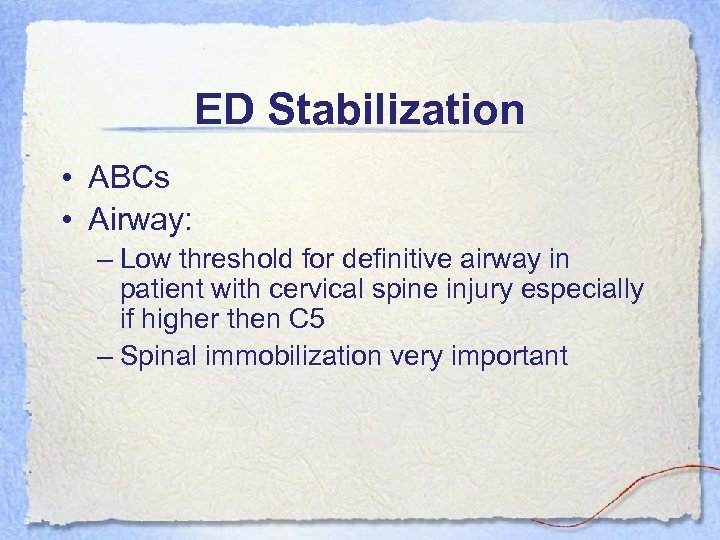

ED Stabilization • ABCs • Airway: – Low threshold for definitive airway in patient with cervical spine injury especially if higher then C 5 – Spinal immobilization very important

ED Stabilization • ABCs • Airway: – Low threshold for definitive airway in patient with cervical spine injury especially if higher then C 5 – Spinal immobilization very important